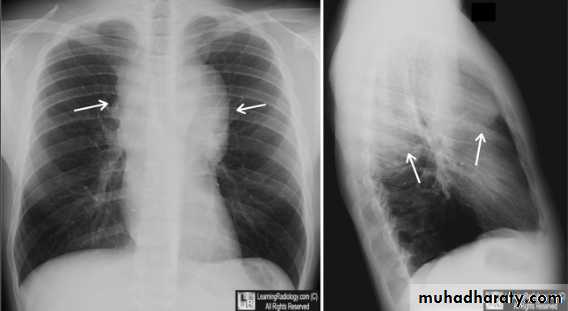

Bilateral enlargement of hilar nodes occurs in:

1- Sarcoidosis, which is far and away the commonest cause.The diagnosis is almost certain if the hilar enlargement is symmetrical and if the patient is asymptomatic, or has either erythema nodosum or iridocyclitis. Simultaneous enlargement of the right paratracheal nodes is common. Lung changes are sometimes visible.

2- Malignant lymphoma.

3- Tuberculosis. African and Asian races show this form of the disease in which substantial nodal enlargement can be a feature. It is rare to see bilateral hilar enlargement due to tuberculosis in Caucasians.

4- Fungal diseases, which are rare causes of bilateral hilar enlargement.

Unilateral rt. Hilar LNE, increase density, lobulated outline.

Identify main lower lobe pulmonary arteries: They can be compared to a little finger pointing downwards and medially. Sometimes, usually on the left side – it can appear only as the proximal phalanx of the finger.Interpretation: If the little finger shadow of the right lower lobe artery is not seen then you must check for evidence suggesting collapse of the right lower lobe.Identify the hilar point: Look for the site where the most superior upper lobe vessel – either vein or artery – crosses the lateral margin of the little finger. The point of crossing is known as hilar point and forms a horizontal “vee” (> or <).Interpretation: The left hilum must never be lower than the right hilum. Whenever a left hilum appears lower than the right hilum – look for other evidence suggestive of: 1- Collapse of either the left lower lobe or of the right upper lobe or 2- Enlargement of the right hilumBilateral hilar LNE